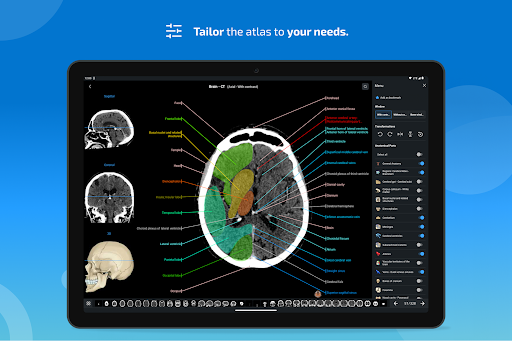

New : You can now filter the modules by region or by content type so you can find the module you are looking for much faster.

-You can now sort modules by modality

- The anatomic view now displays more labels